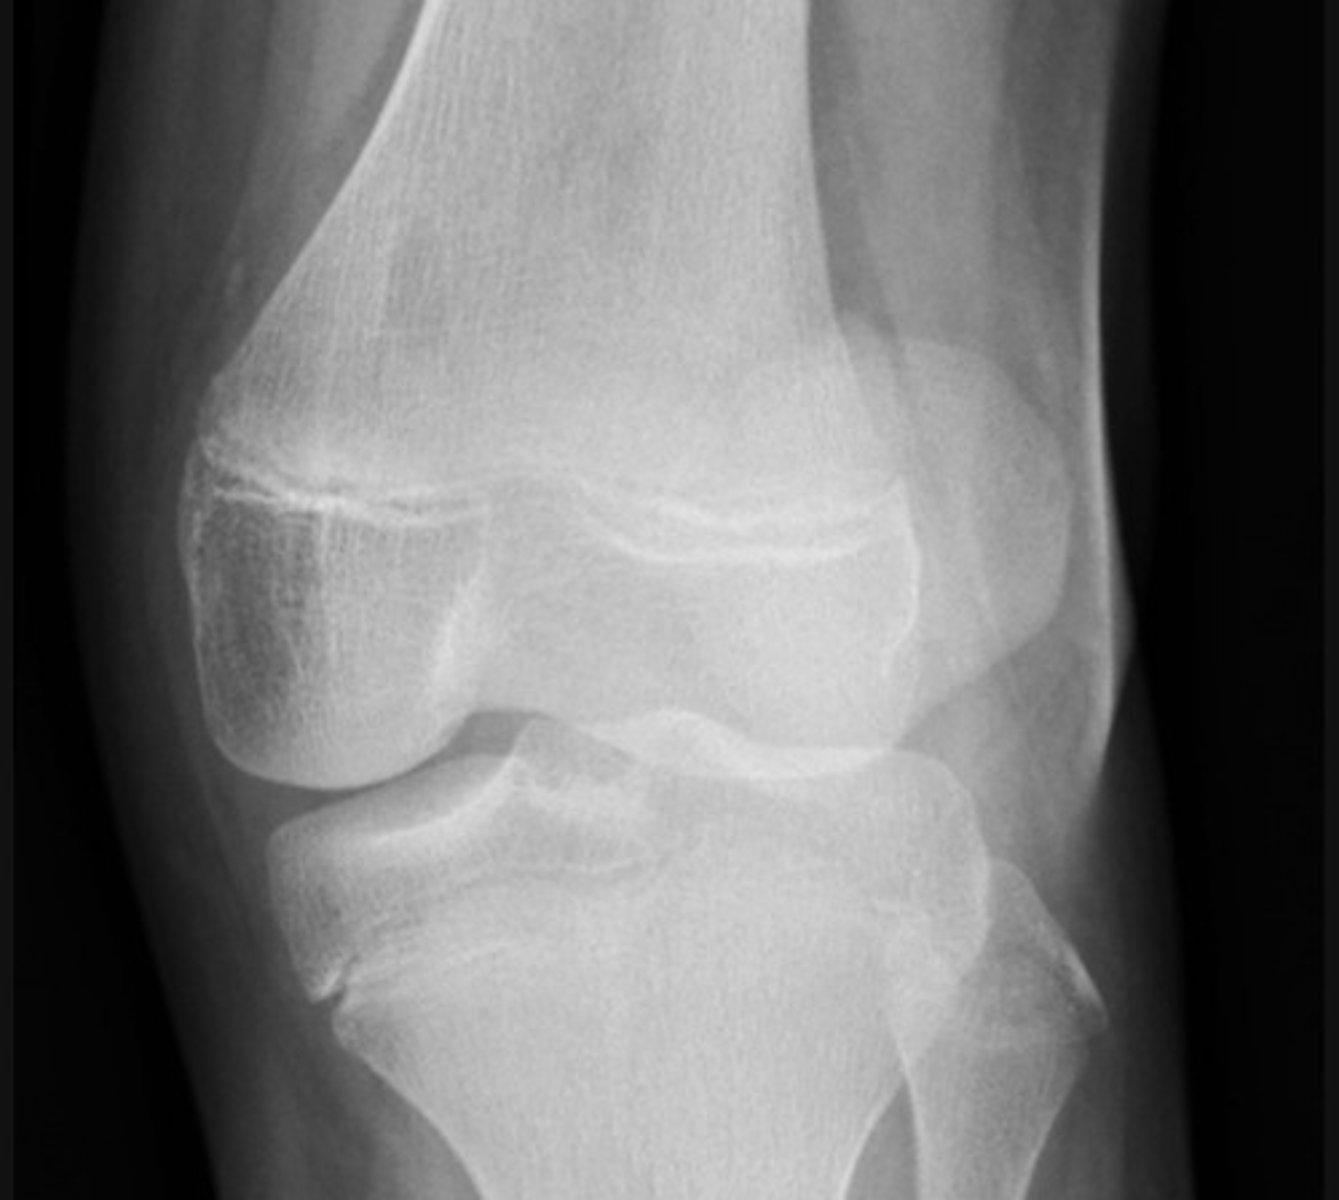

severely comminuted fracture of the tibial plateau and a lipohaemarthrosis

Lateral patella dislocation